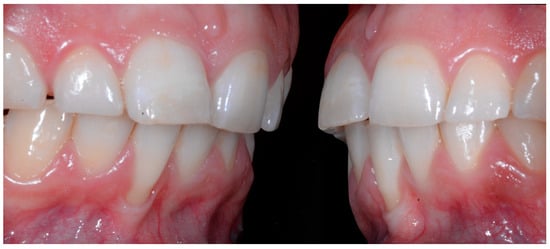

A 26-year-old female patient was referred by her general dentist for suspected wire syndrome. Orthodontic treatment had been performed 10 years previously, and bonded restorations had been fitted at the end of the treatment. The patient mentioned several episodes of breakage/adhesion, without further details. She has good oral hygiene and a right and left Class I (Figure 5).

Figure 5.

Intermediate wire syndrome. Frontal and lateral views.

In the mandible, the retainer was broken distal to 42 and, despite being intact on 33, this tooth had increased visibility of its vestibular surface compared to its contralateral tooth (differential torque). Finally, teeth 31 and 41 also showed a difference in the visibility of their vestibular surfaces (differential torque). Ultimately, the patient was diagnosed with an X-effect wire syndrome on 21, an X-effect wire syndrome on 41, and a Twist-effect wire syndrome on 33.